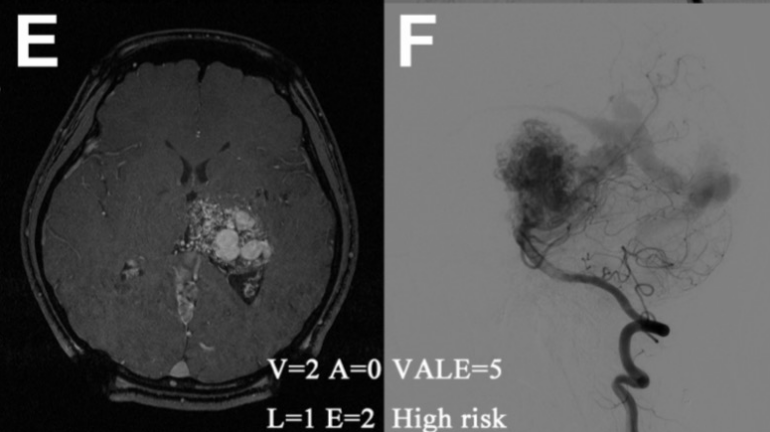

典型案例:E-F,1例未破裂AVM伴右侧肢体无力,经VALE模型(脑室系统受累= 2,静脉瘤= 0,深部位置= 1,单一深静脉引流= 2,VALE=5)评估为高危组,诊断后8.17年首次出血,并在接下来5年内反复破裂3次。